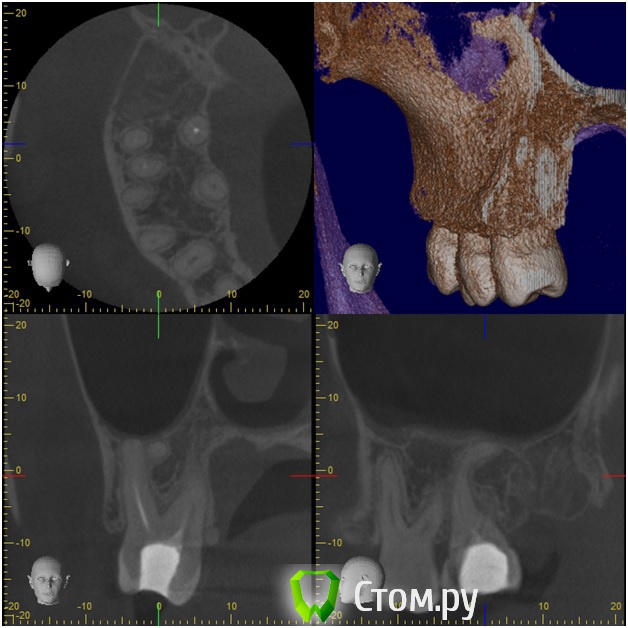

Анатолий М Опубликовано 21 апреля, 2014 Поделиться Опубликовано 21 апреля, 2014 Добрый день. Помогите пожалуйста.17 зуб (верхняя семерка с права). Пол года назад был депульпирован. Все это время присутствуют боли под этим зубом по симптомам очень похожие на кисту (распирание, боль ноющая не сильная, то появляется то сама собой изчезает. при перкуссии 17 зуб слегка болезненный). 2 месяца наза решили зуб перелечить. На ОПТГ ситуация до перелечивания. По снимку видно что первоначальное лечение было проведено плохо. Корни были плохо пройдены и плохо заполены цементом.Месяц хождения с гидроокисью кальция на воде никакого эфекта не дали. Врачи считают что под зубом есть киста. И предлагают удалить зуб. Так как перелечивание не помогло.Прилагаю снимок КЛКТ после лечения. Зуб все еще под временной пломбой. Из трех врачей лишь один разгледел на КЛКТ кисту под 17 зубом. Два других ни на КЛКТ ни на прицельных никакой кисты не видят. Направили к неврологу. Думают что киста если она и есть (в чем они не уверены) не дает имеющихся симптомов.Пожалуйста посмотрите на КЛКТ. Есть ли там киста или нет? И могут ли боли быть от нее?Заранее спасибо. Ссылка на комментарий

Анатолий М Опубликовано 21 апреля, 2014 Автор Поделиться Опубликовано 21 апреля, 2014 КТ до лечения. Эту пломбу вскрыли. Каналы полностью проработали и поставили лекарство. 3 раза меняли по принципу 3дня+3нед+4недели. Ниже приложен КТ контрольный через месяц лечения. Сейчас в каналах лекарство. Кт после постоянного пломбирования корневых каналов? Есть снимки во время лечения и контрольный после? Ссылка на комментарий

Анатолий М Опубликовано 21 апреля, 2014 Автор Поделиться Опубликовано 21 апреля, 2014 Снимок во время лечения делали? Коффердам и оптика использовались? На кт в тех срезах что Вы выложили кисты не вижу Снимки во время лечения делали три раза прицельные с иголками в каналах. Но они остались у врача. У меня их нет. Но она по ним кисты не видела. Коффердам использовали только при первом посещении когда вскрывали старую пломбу и прорабатывали каналы. При последующих посещениях при смене лекарст его не использовали так как кольцо на зубе плохо держалось и постоянно слетало. Плюс травмировало десну.Микроскоп использовали все три раза. По словам врача (врач высшей категории эндодонтист зав отделением):При вскрытии старой пломбы каналы практически не заполены цементирующим составом. Иструмент при вскрытии пломбы в каналы проваливался. Хотя стояла постоянна пломба. Из трех каналов лишь один был проработан до верхушки корня. Два других либо до половины либо на треть. Врачь полностью прошла все каналы и даже залезла за апекс. туда при первом пломбировании врач даже не пыталась лезть. При третьем посещении врач констатировала что каналы чистые. Никаких признаков инфекции нет. И белезненная перкуссия от чего то другого. Специально проводила ревизию каналов при втором и третьем посещении без анастезии что бы понять где болит. Но так и не поняла. Повела на консультацию к профессору в их стоматологи. Посмотрев контрольную КТ он сказал что там киста и надо удалять зуб! Похоже что мой врач с ним не очень согласна, хотя и спорить не стала поэтому отправила меня на консультацию к неврологу. Ниже срезы конрольного КТ после месяца лечения гидрооксидом кальция на воде. Срезы по дуге. Сделал как смог. Шаг срезов как я понимаю 1мм. Линия по перек дуги снимок номер 1 (см нумерацию в конце названия файла) Ссылка на комментарий